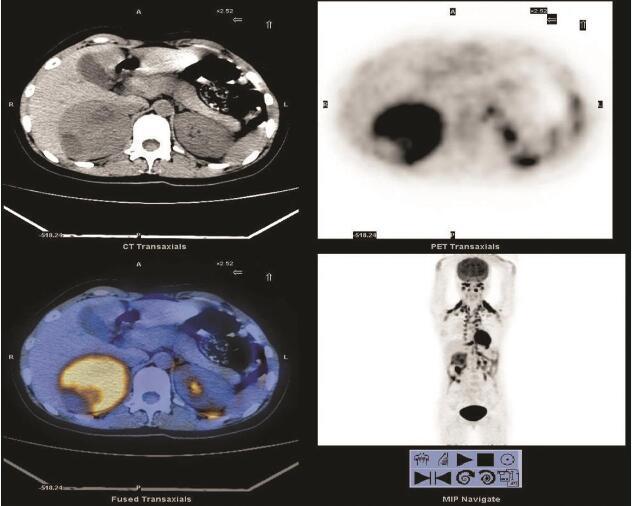

肾脏淋巴瘤PETCT检查案例

554x471 - 451KB - PNG